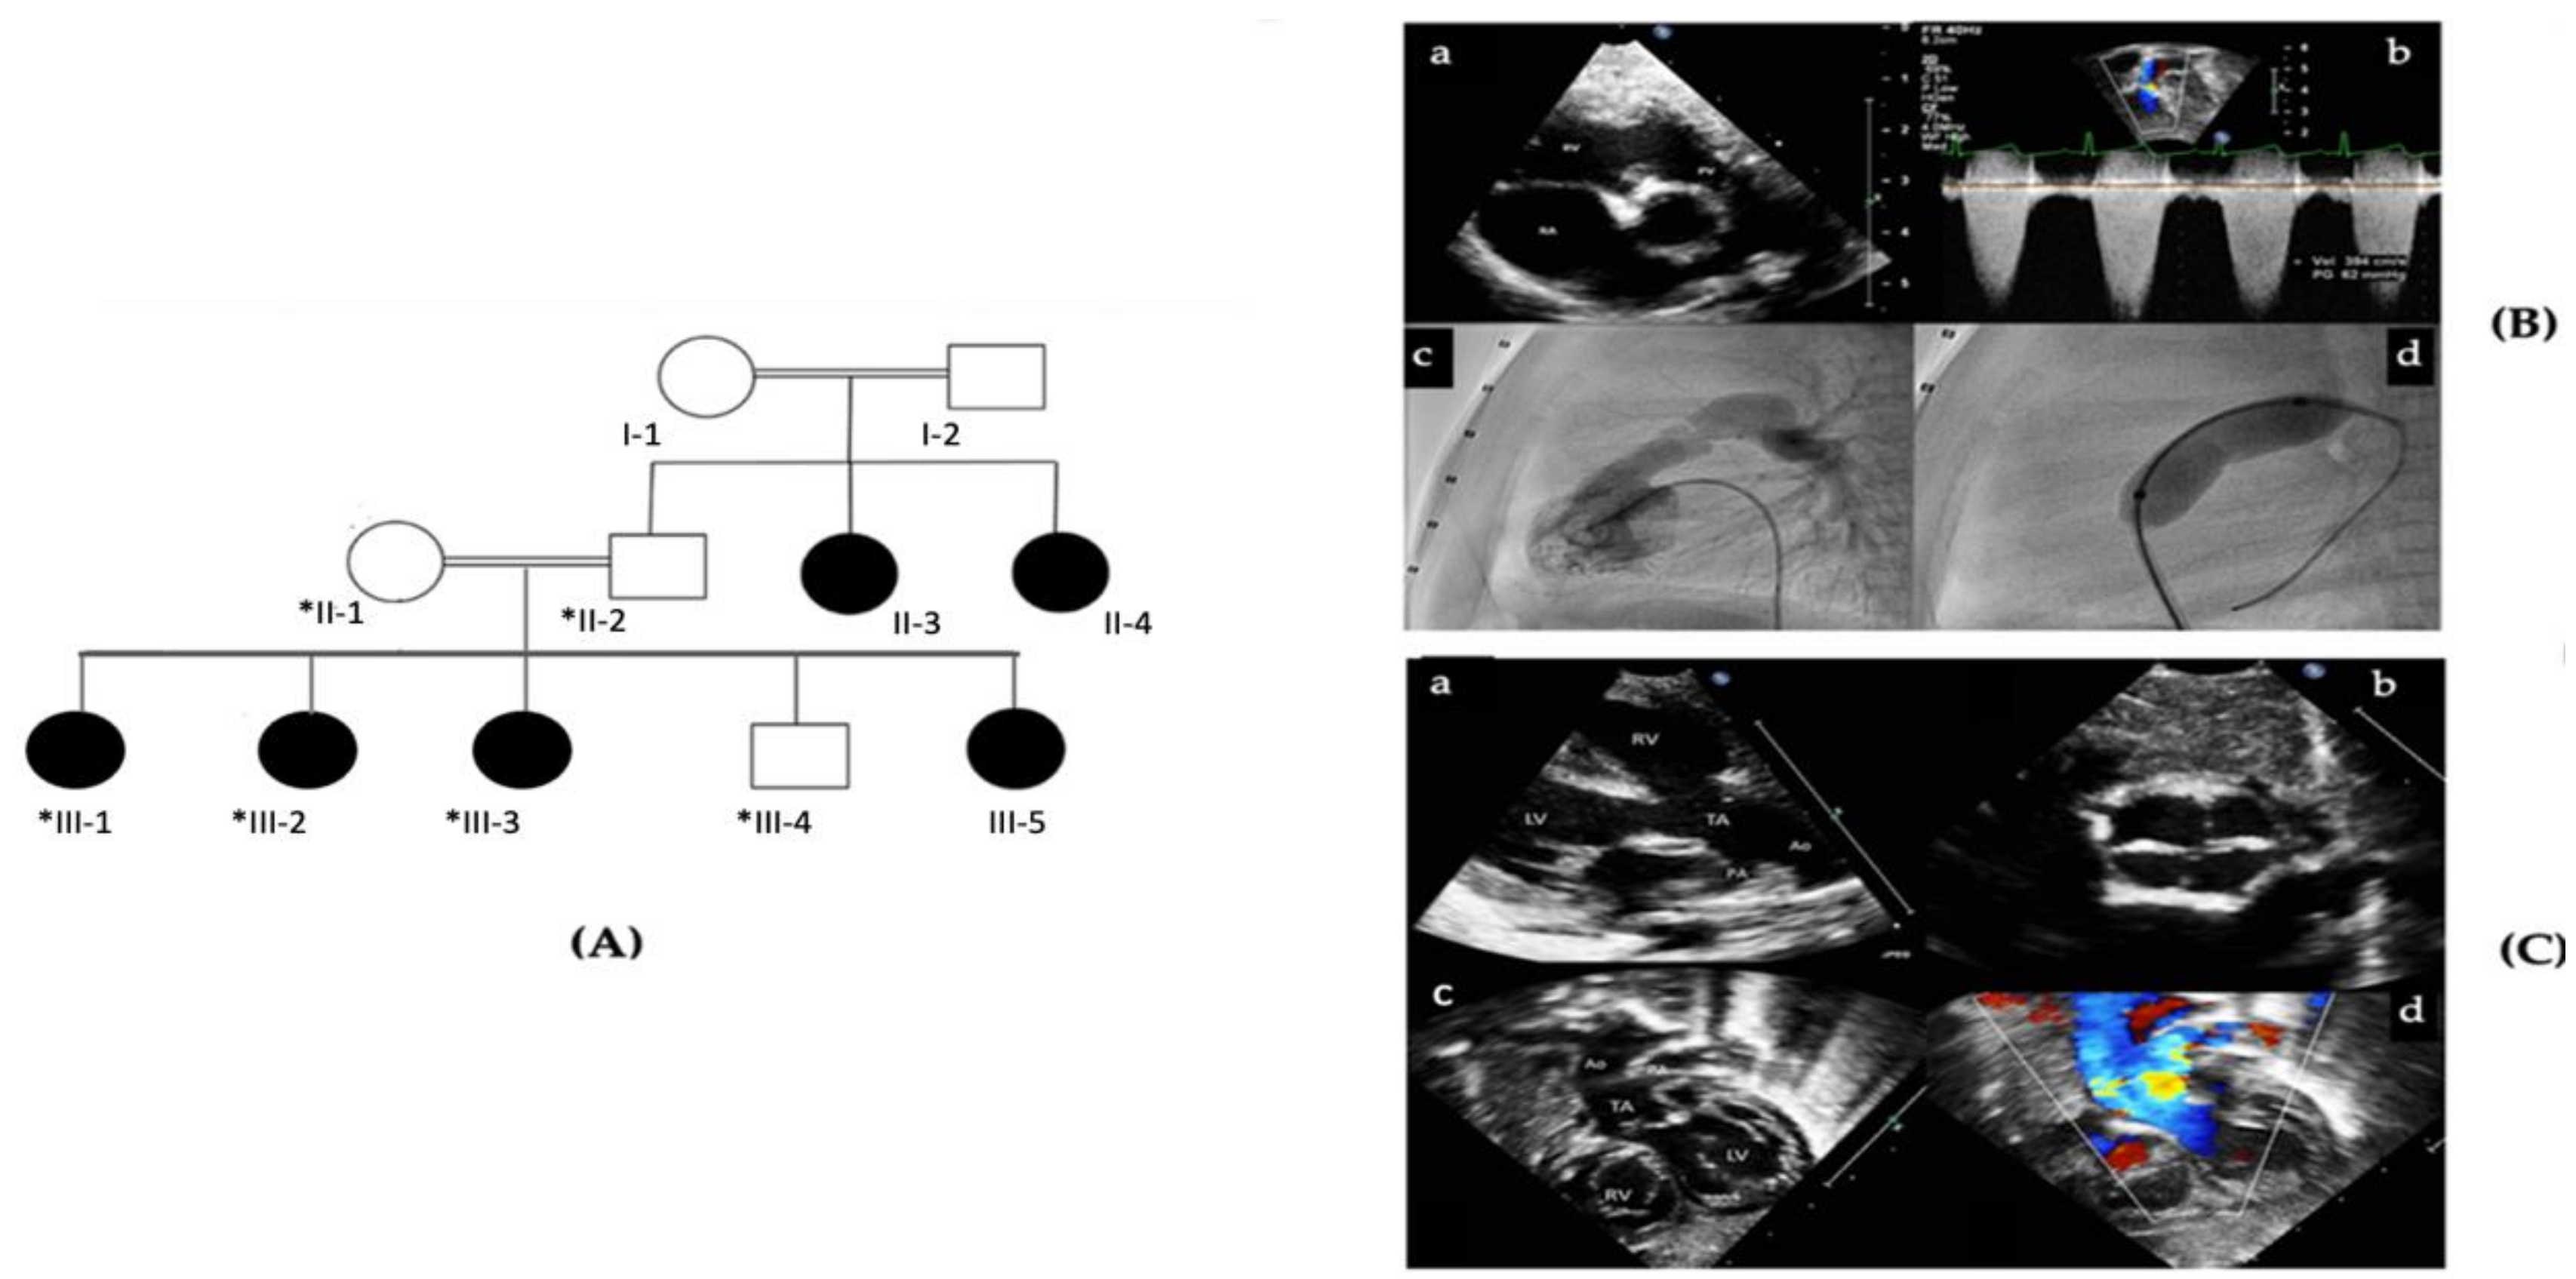

| Patient II-3, II-4 | Patient III-1 | Patient III-2 | Patient III-3 | |

| Age | NA | 10 | 9 | 6 |

| Gender | Females | Female | Female | Female |

| Weight | NA | 40 | 29.6 | NA |

| Height | NA | 148 | 138.5 | NA |

| Cardiovascular Symptoms | NA | Asymptomatic | Respiratory distress | Asymptomatic |

| Clinical Diagnosis | Septal Defects (not specified) | Pulmonary stenosis | TA type II and VSD | ASD |

| Mental Development | Normal | Normal | Normal | Normal |

| Neurological Abnormalities | Normal | Normal | Normal | Normal |

| Motor development | Normal | Normal | Normal | Normal |